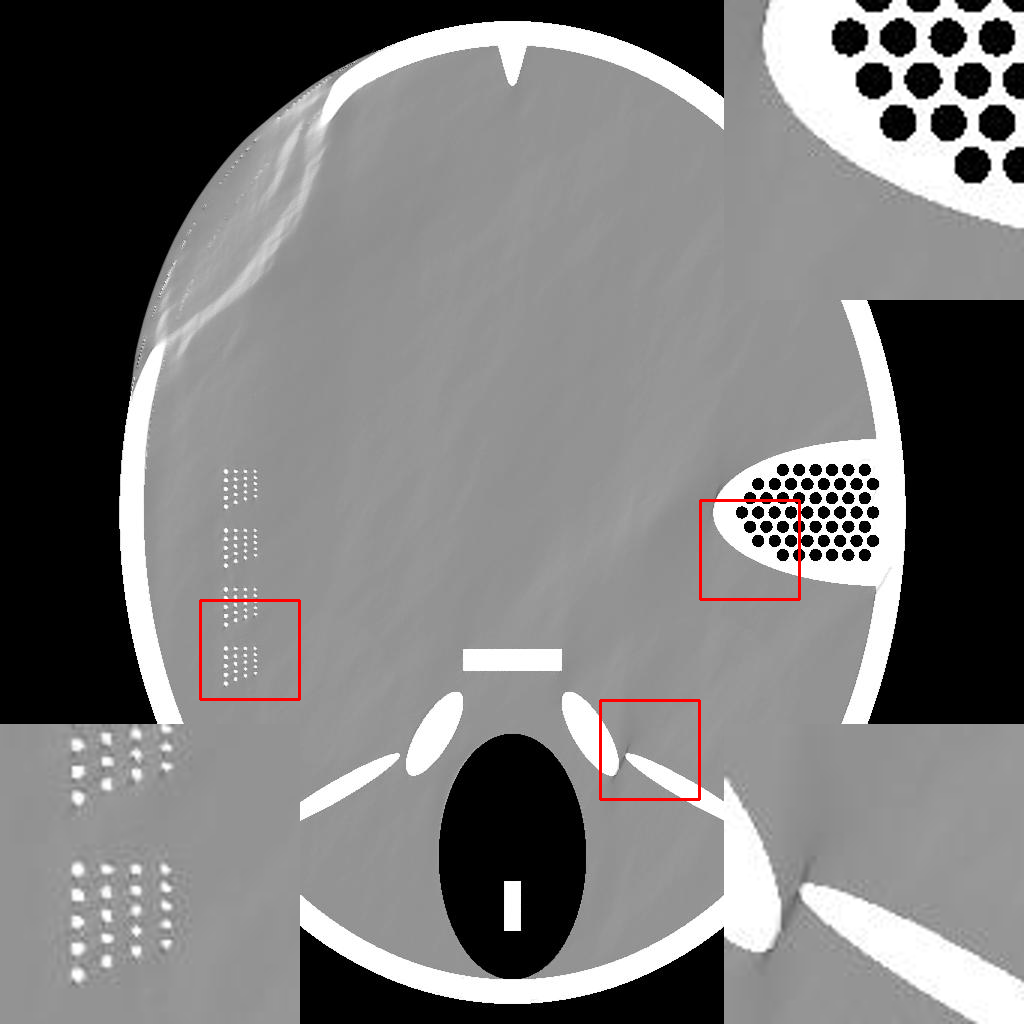

IV-A Effect of Residual Back Projection in Reconstruction

To demonstrate the efficacy of the RBP connection and show the details of the RBP-DIP’s reconstruction process, the procedure of a limited-angle CT reconstruction is shown in Fig.2. Its first row illustrates the results of reconstruction across different iterations, whereas the second row presents the respective inputs fed into the U-net, which are updated through the RBP connection. Here, the number of views is set to , uniformly distributed from to . This scenario presents a challenging limited-angle CT reconstruction problem.

In the first iteration, as depicted in Fig.2a, the input image undergoes an update via the RBP connection prior to being fed to the U-net. Thus, this input is the normalized first iteration output of the implemented IR algorithm (normalized back projection image in our case). The output appears completely randomized since the entire neural network is randomly initialized.

In the 10th and 20th iterations (Fig.2b and Fig.2c), the DIP property effectively expedites the recovery of the object over its support. Of note are lack of artifacts commonly caused by having missing views in the data. The input images highlight the region which can be relatively accurately reconstructed by conventional IR methods. This can be used to guide the model in the later iteration. In our experiment, the model capitalizes on the input images more when reconstructing the upper-left and lower-right segments of the image, while relying predominantly on the DIP property for the reconstruction of the upper-right and lower-left parts.

In the 2000th iteration, as depicted in Fig.2d, the reconstruction result becomes relatively artifact-free. At this stage, the network input primarily emphasizes the edges to help the method improve the supporting area. Moreover, the RBP connection can rectify artifacts specific to convolutional neural networks. Evidence of this can be observed in the second row of Fig.2c, Fig.2d, and Fig.2e, which display distinct horizontal and vertical patterns. These patterns are mainly caused by the convolution operation in the U-net. In other words, the DIP and RBP parts of the proposed framework are able to mutually rectify each other’s errors. Consequently, a high-quality reconstruction result is attainable, as shown in Fig.2e.